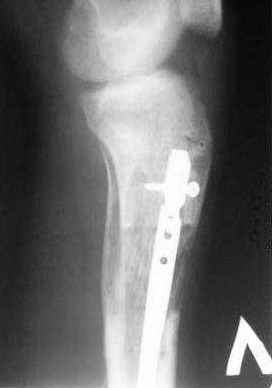

5, 6 - через 2,5 мес после травмы выполнен закрытый остеосинтез блокируемым штифтом.